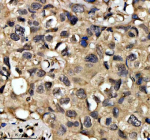

Immunohistochemical staining of QKI using anti-QKI antibody. QKI was detected in a paraffin-embedded section of human glioma tissue. Heat mediated antigen retrieval was performed in EDTA buffer (pH 8.0, epitope retrieval solution). The tissue section was blocked with 10% goat serum. The tissue section was then incubated with 2 ug/ml rabbit anti-QKI antibody overnight at 4oC. Peroxidase Conjugated Goat Anti-rabbit IgG was used as secondary antibody and incubated for 30 minutes at 37oC. The tissue section was developed using an HRP secondary and DAB substrate.